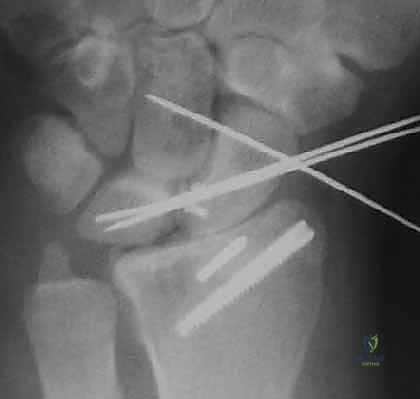

الخطوة الثانية: إدخال المنظار (Portals)

يقوم الدكتور هطيف بعمل 2 إلى 3 ثقوب دقيقة جداً (Portals) في ظهر الرسغ. يتم إدخال الكاميرا من ثقب، وأدوات العمل الجراحية الدقيقة من الثقوب الأخرى.

الخطوة الرابعة: رد الكسر تحت الرؤية المباشرة

باستخدام أدوات دقيقة، يتم تحريك القطع العظمية المكسورة وإعادتها إلى مكانها الطبيعي. يراقب الجراح العملية عبر شاشة المنظار ليتأكد من أن السطح المفصلي أصبح مستوياً تماماً بنسبة 100%.

الخطوة الخامسة: التثبيت الداخلي

بمجرد استعادة الشكل التشريحي، يتم تثبيت العظام. قد يتم استخدام أسلاك كيرشنر (K-wires)، مسامير دقيقة، أو شريحة معدنية داعمة (Volar Plate) توضع من خلال شق صغير منفصل لضمان ثبات الكسر التام. يتم أيضاً خياطة أي تمزق في الأربطة إن وجد.